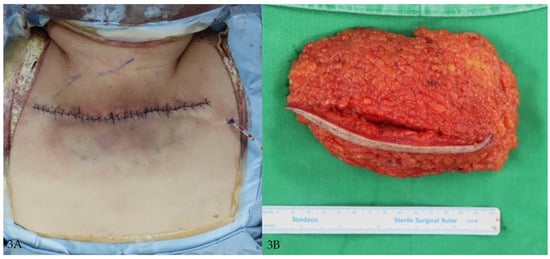

3.1.1. Case 1